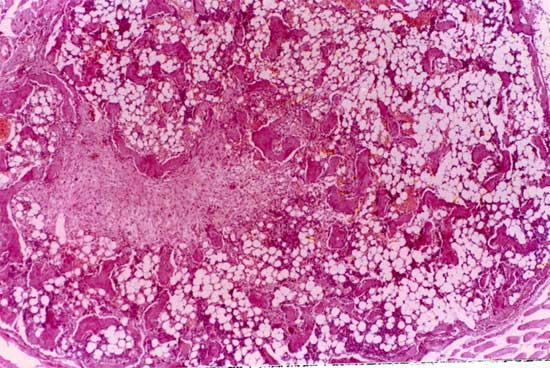

异种骨取之于动物,来源丰富,易于大量获取和加工贮存,用作植骨材料有巨大开发潜力,但未经处理的异种骨植入体内可引起强烈的免疫排斥反应,采用多种理化方法处理,在消除其抗原性的同时也使有益的生物活性物质破坏殆尽,这就是异种骨长期不能应用于临床的原因。 如果将成骨活性物质浓集,与经过处理的异种骨松质骨复合,后者是良好的缓释载体,具有高效诱导成骨能力,且移植骨之尺寸和生物学活性可根据缺损大小及个体需要而制作成合适的“预制件”。这是将BMP与适当载体结合的一种新方式,为更好地利用异种骨开辟了一条新途径。 为了进一步提高BMP及其复合材料应用于骨折愈合与骨缺损修复能力,我们将复合BMP的异种骨与自体成骨细胞共同培养,使细胞长入骨孔内,再将骨块植入体内,获得良好成骨效果。

复合BMP的异种骨与自体成骨细胞共同培养, 使细胞长入骨孔内,再将骨块植入体内,获得良好成骨效果